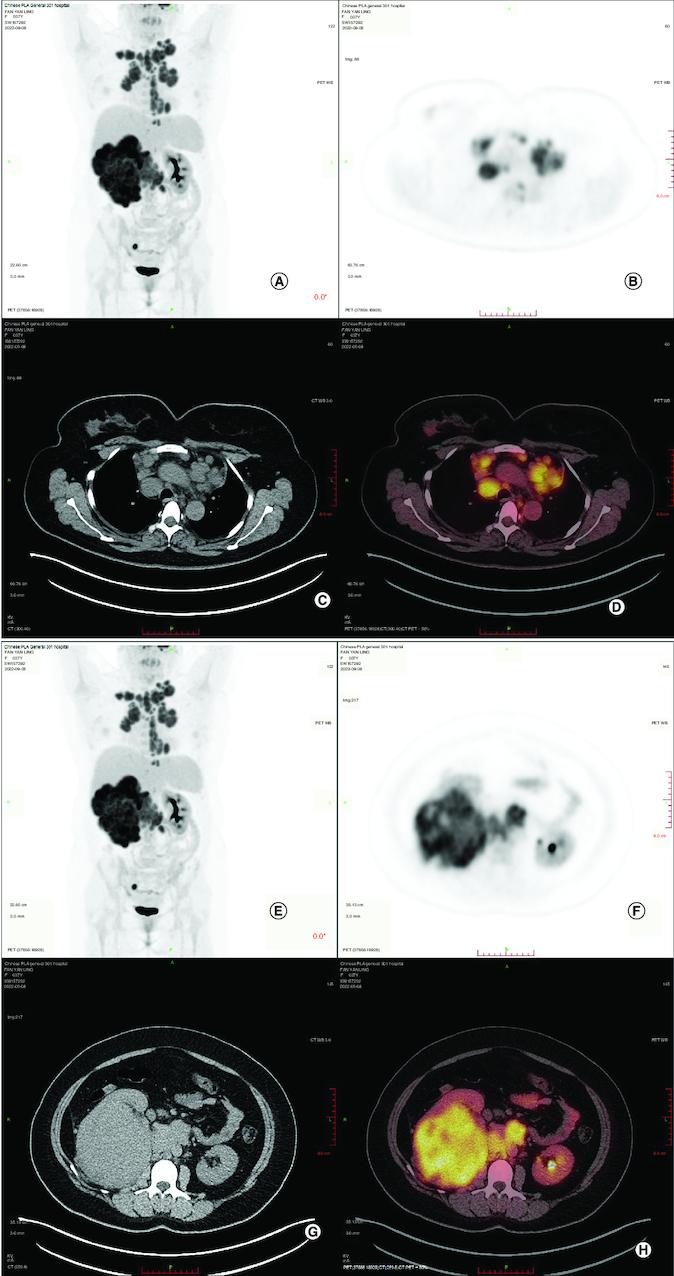

采用化疗、免疫治疗和靶向治疗的转移性成人肾母细胞瘤:一例报告

Metastatic adult Wilms' tumor managed by chemotherapy, immunotherapy and target therapy: a case report.

Wilms' tumor is a rare type of tumor in adult. Herein, we reported a case of 37-year-old female with adult Wilms' tumor (AWT) admitted in our institution. After a multidisciplinary team discussion, she underwent receiving immunotherapy plus chemotherapy and VEGF-targeted therapy. The tumor got smaller obviously after eight cycles of treatment. Our present case suggested that immunotherapy and anti-angiogenesis combined with chemotherapy is promising new approach for treating AWT. Moreover, we review the literatures reporting AWT with the purpose to improve the understanding of AWT treatment.

摘要

肾母细胞瘤在成人中是一种罕见的肿瘤类型。在此,我们报告了一例37岁成年女性肾母细胞瘤(AWT)患者入住我院的病例。经过多学科团队讨论后,她接受了免疫治疗加化疗以及VEGF靶向治疗。经过八个周期的治疗后,肿瘤明显缩小。我们目前的病例表明,免疫治疗、抗血管生成联合化疗是治疗AWT有前景的新方法。此外,我们回顾了报道AWT的文献,以增进对AWT治疗的理解。